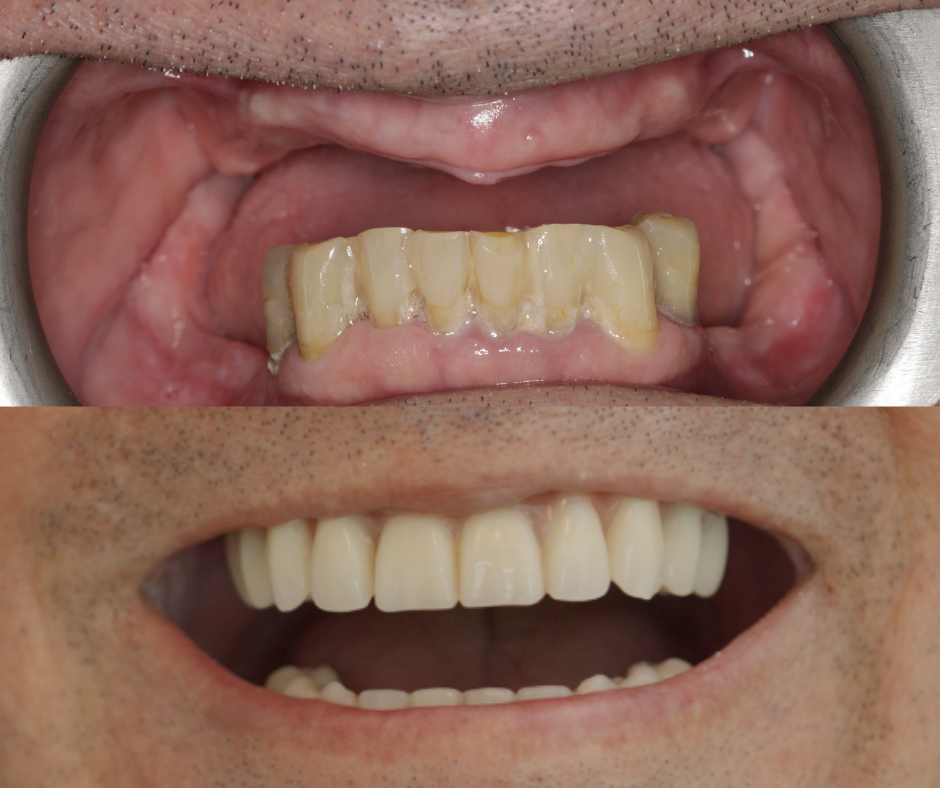

Mirosław ma 67 lat, kocha rower, wolność i życie. Ale przez lata unikał… uśmiechu. Dziś znów się uśmiecha. Dlaczego? Bo zdecydował się na leczenie metodą, która pozwoliła mu odzyskać komfort i pewność siebie. Mirek to osoba aktywna, pełna pasji do życia – szczególnie do kolarstwa.

W przypadku Pana Mirosława istotne było to, że jest osobą bardzo aktywną. Tradycyjna proteza nie zapewniała mu odpowiedniej stabilności – podczas wysiłku potrafiła się przemieszczać. Po leczeniu metodą All-on-4 wrócił do aktywności bez obaw i z uśmiechem.

W ciągu jednego dnia zabiegowego, po usunięciu zębów (jeśli to konieczne), możliwe jest wszczepienie implantów i osadzenie tymczasowego mostu, który umożliwia mówienie, jedzenie i uśmiechanie się już po kilku dniach.

Po około 4 miesiącach, gdy implanty zintegrują się z kością, wykonywana jest ostateczna praca protetyczna – Malo Clinic Bridge, indywidualnie dopasowana do pacjenta. W Malo Clinic każdy pacjent implantologiczny jest zobowiązany do:

Dla wielu pacjentów najważniejsze są efekty, które widzą w lustrze – naturalny wygląd, swobodny uśmiech, komfort jedzenia i pewność siebie w relacjach z innymi. Jednak jako lekarze stomatolodzy, naszym głównym celem są korzyści medyczne, które ta metoda może zapewnić: przywrócenie prawidłowej funkcji żucia, stabilizacja zgryzu, wsparcie dla tkanek twarzy, co zapobiega ich zapadaniu się, ochrona przed dalszym zanikiem kości i wiele innych.